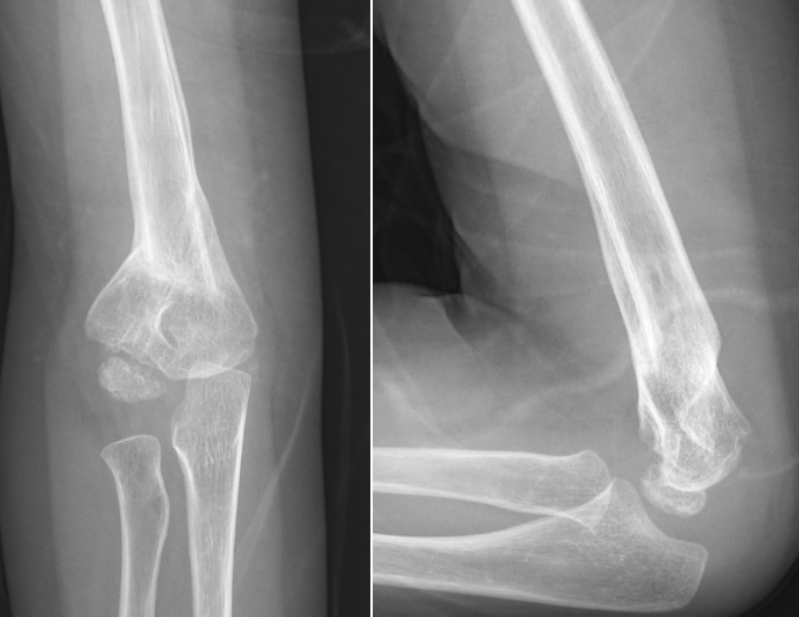

病例3:小玉(化名)、女、4岁,2年前因摔伤致“右肱骨髁上骨折”,于当地医院行手法复位石膏外固定,石膏固定一个月拆除外固定后逐渐发生右肘内翻畸形。

拆除石膏后X线片

该患者的情况跟小红的一样,都是治疗不规范引起的肘内翻畸形。该病例虽然年龄较小,但肘内翻畸形严重,保守治疗2年后未见明显改善,遂于行手术治疗。

术后X线片

取完钢针后随访